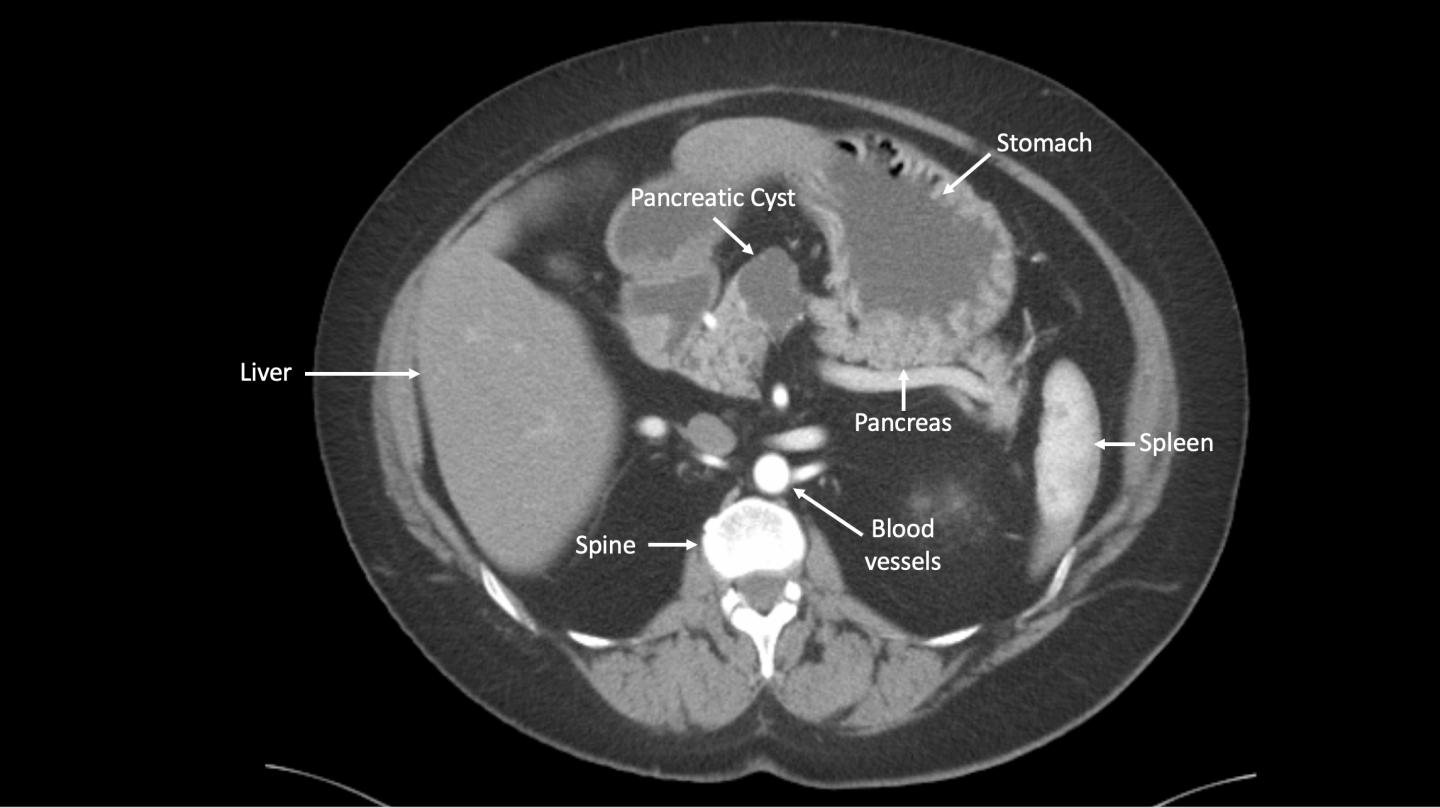

Test shown to improve accuracy in identifying precancerous pancreatic cysts

image: CT of the pancreas with cyst

In a proof-of-concept study, an international scientific team led by Johns Hopkins Kimmel Cancer Center researchers has shown that a laboratory test using artificial intelligence tools has the potential to more accurately sort out which people with pancreatic cysts will go on to develop pancreatic cancers.

The test, dubbed CompCyst (for comprehensive cyst analysis), incorporates measures of molecular and clinical markers in cyst fluids, and appears to be on track to significantly improve on conventional clinical and imaging tests, the research team says.

The CompCyst test, developed by the Johns Hopkins Kimmel Cancer Center-led investigators, was created with patient data including clinical impressions and symptoms, images from CT scans and molecular features such as DNA alterations within cyst fluid.